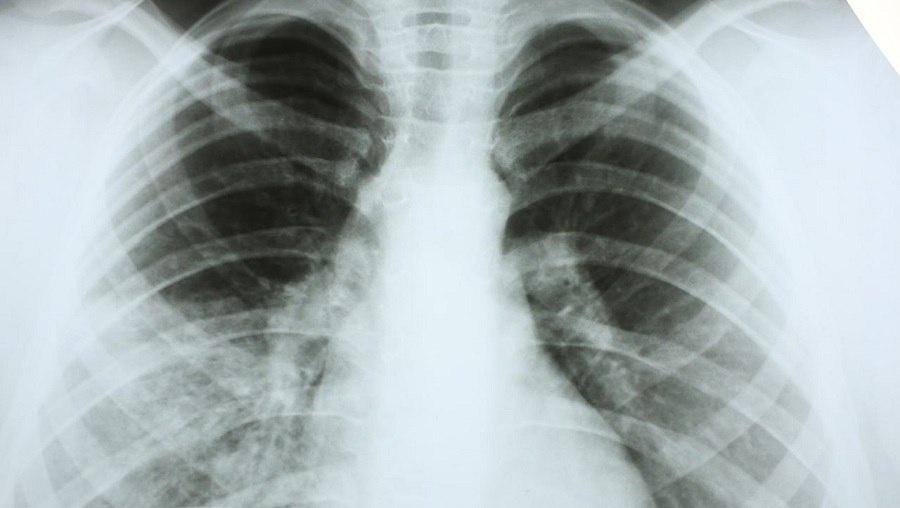

В Республике Алтай зафиксирована тревожная статистика по пневмонии. За 10 месяцев 2025 года диагноз подтвержден у 1185 человек. Только на прошлой неделе госпитализированы 27 пациентов с внебольничной пневмонией, среди них — четверо детей.

Пневмония остается серьезным заболеванием, которое легко спутать с обычной простудой. Однако последствия промедления с лечением могут быть тяжелыми, о чем свидетельствует стопроцентная госпитализация всех выявленных на прошлой неделе случаев.